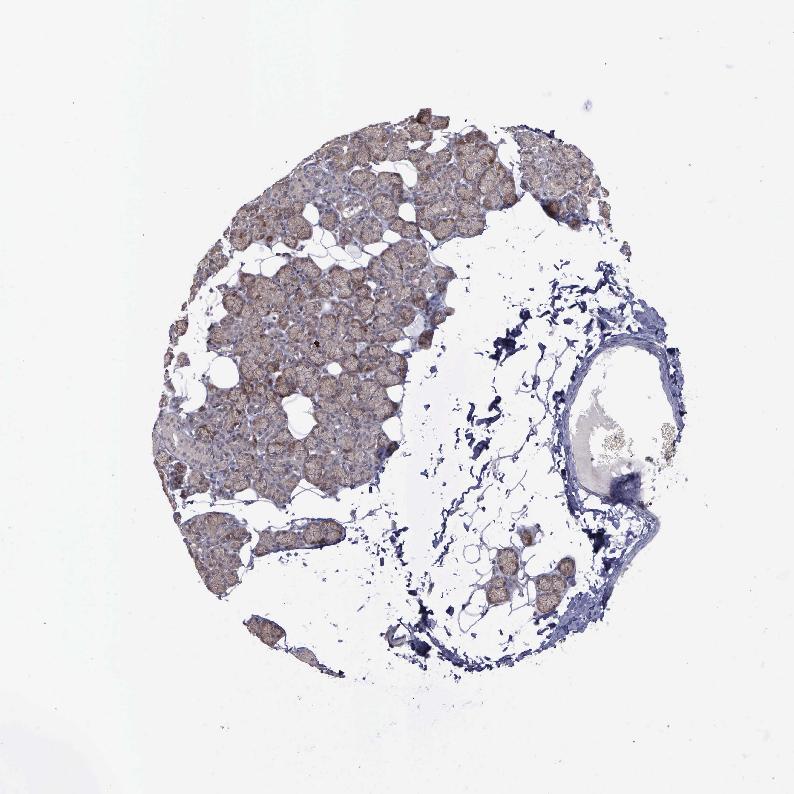

SALIVARY GLAND - Antibody stainingi

Antibody staining in the annotated cell types in the current human tissue is reported as not detected, low, medium, or high, based on conventional immunohistochemistry profiling in selected tissues. This score is based on the combination of the staining intensity and fraction of stained cells.

Each image is clickable and will lead to virtual microscopy that enables deeper exploration of all samples and also displays staining intensity scores, fraction scores and subcellular localization as well as patient and tissue information for each sample.

Antibody HPA000942

Glandular cells Low